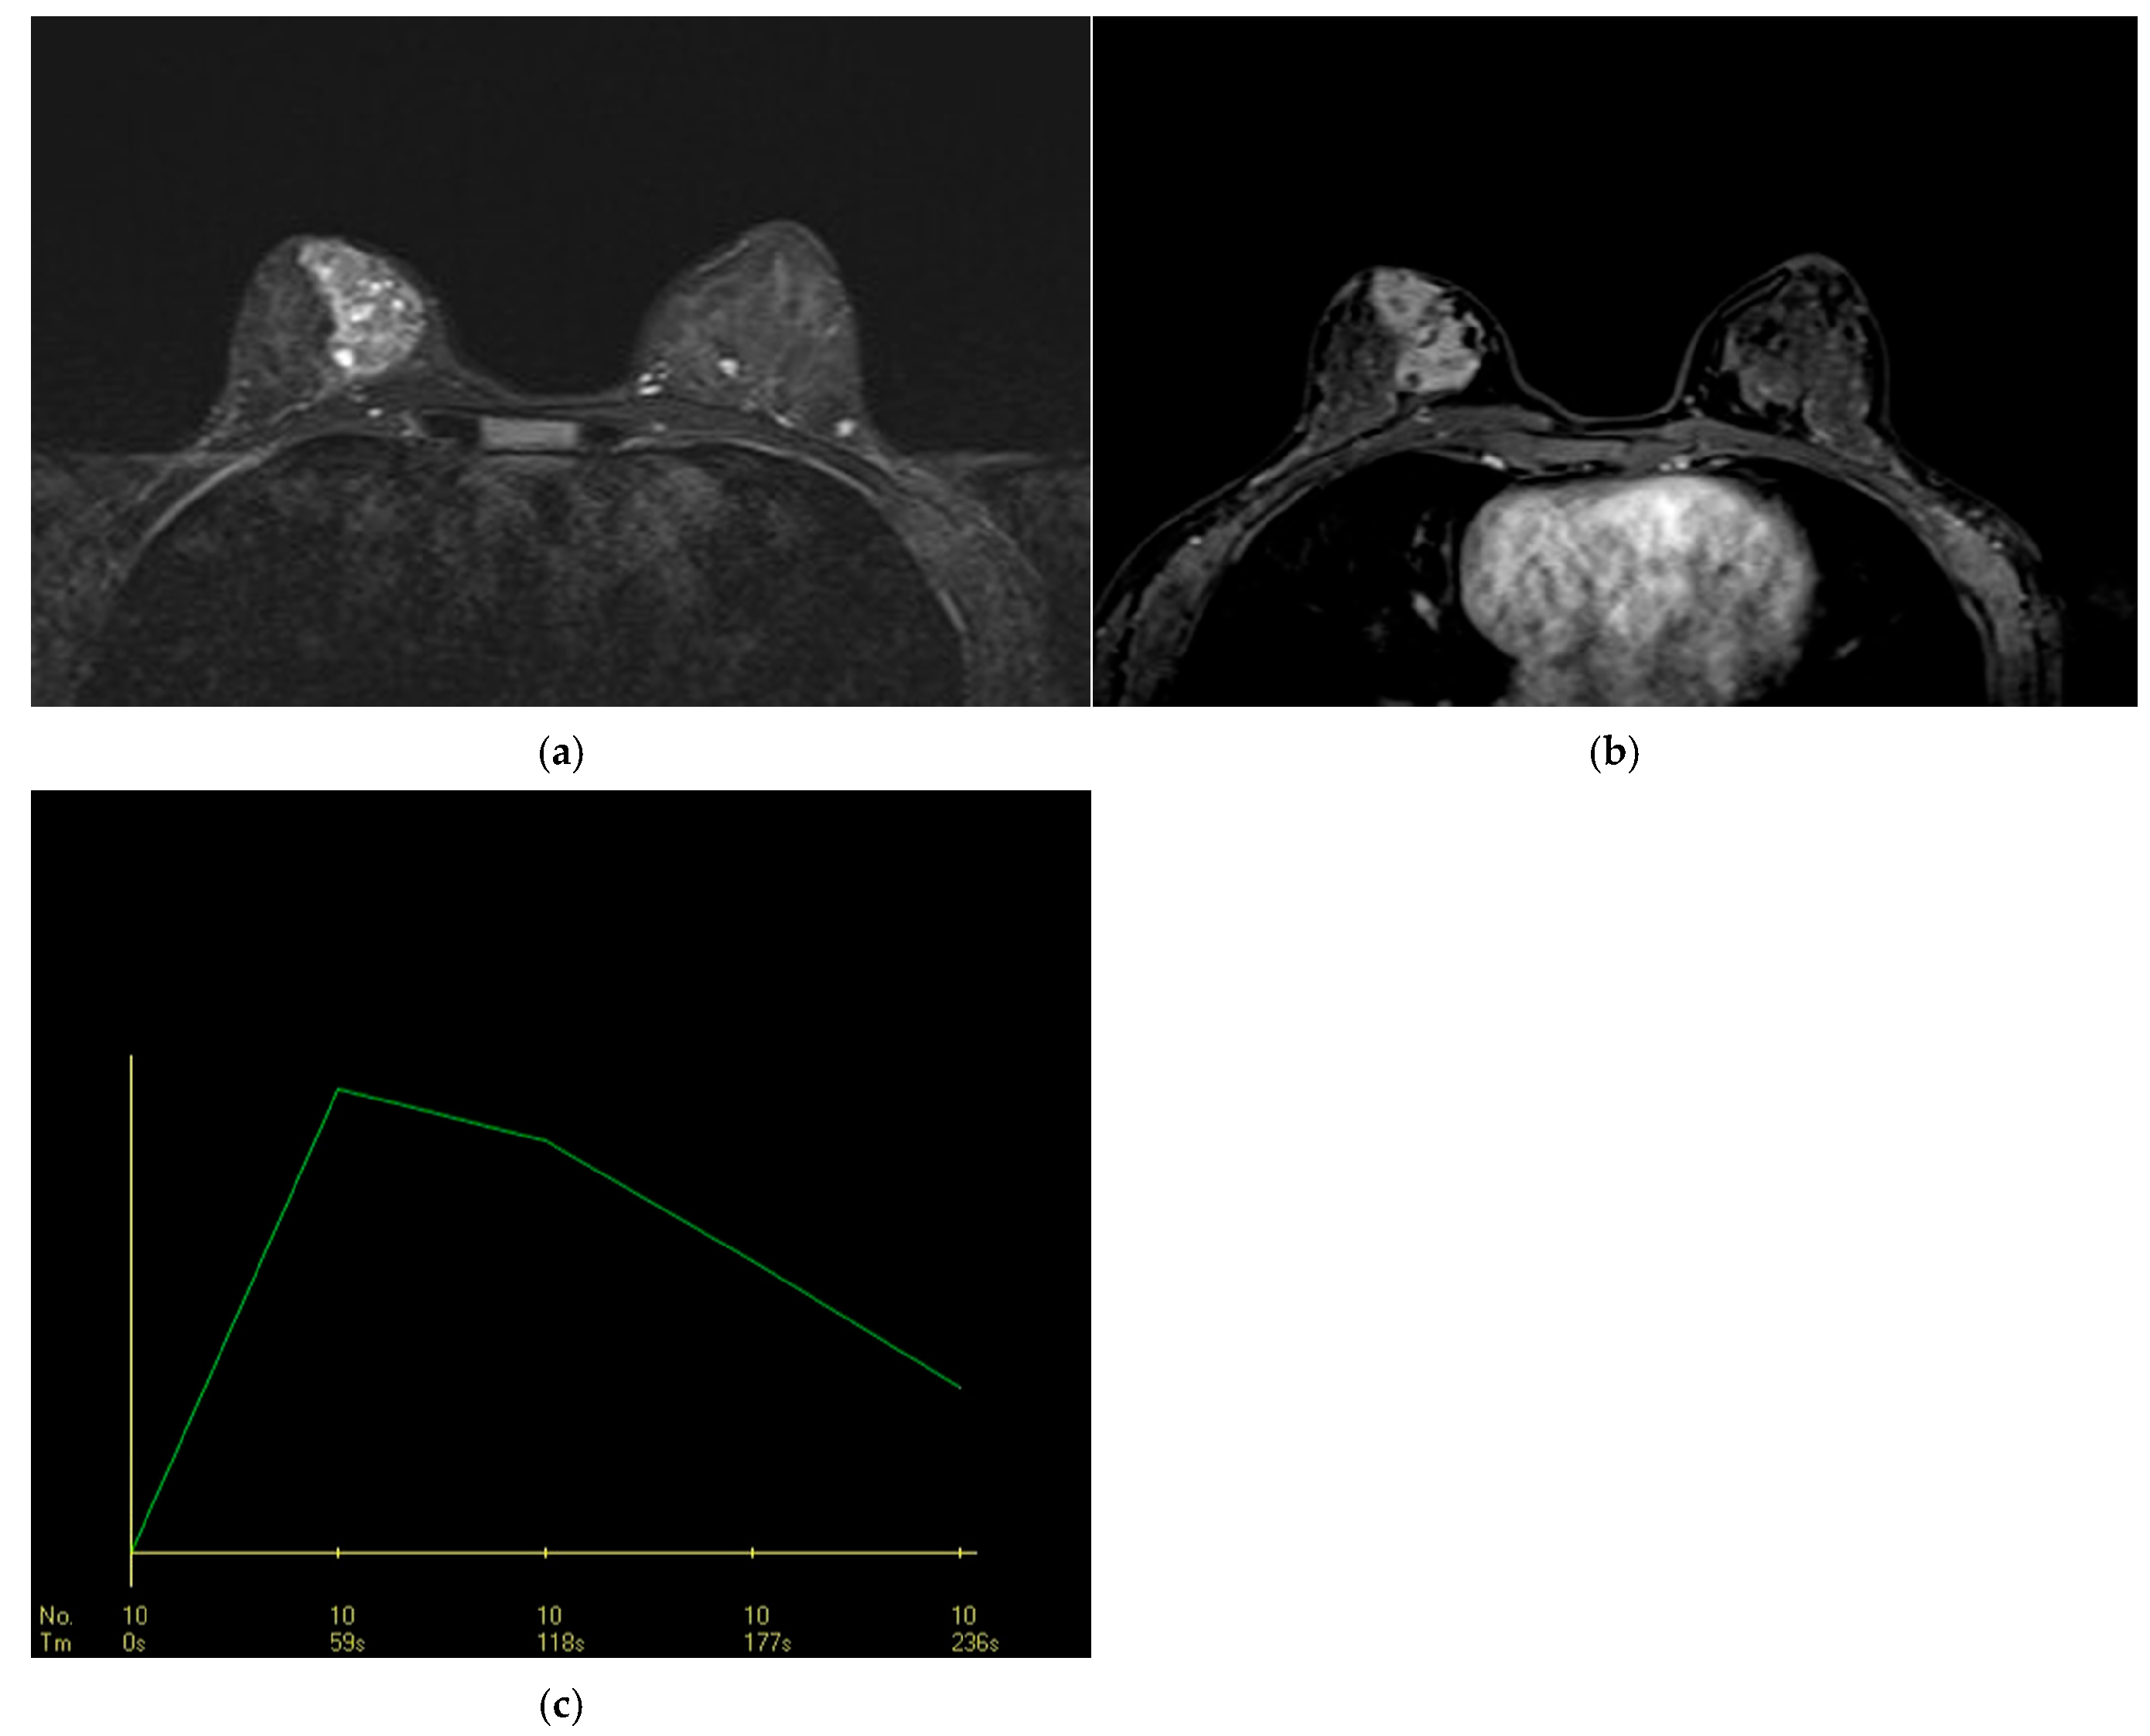

3.2.4. DCE-MRI Kinetic Features

| Dynamic curve in the initial phase * | <0.001 * | ||

| Slow * | 20 (60.6%) | 12 (17.1%) | <0.001 * |

| Moderate | 7 (21.2%) | 16 (22.9%) | 0.852 |

| Rapid * | 6 (18.2%) | 42 (60%) | <0.001 * |

| Dynamic curve in the delayed phase * | 0.009 * | ||

| Persistent | 15 (45.5%) | 17 (24.3%) | 0.030 * |

| Plateau | 16 (48.5%) | 31 (44.3%) | 0.690 |

| Washout | 2 (6.0%) | 22 (31.4%) | 0.004 * |

| Slow * | 0.134 | 0.053 | 0.343 | 0.000 * | 0.194 | 0.049 | 0.770 | 0.020 |

| Moderate | 1.101 | 0.403 | 3.003 | 0.852 | ||||

| Rapid * | 6.750 | 2.469 | 18.451 | 0.000 * | 5.133 | 1.164 | 22.637 | 0.031 |

| Dynamic curve in the delayed phase | ||||||||

| Persistent * | 0.385 | 0.160 | 0.925 | 0.033 * | ||||

| Plateau | 0.845 | 0.368 | 1.936 | 0.690 | ||||

| Washout * | 7.104 | 1.559 | 32.363 | 0.011 * | ||||